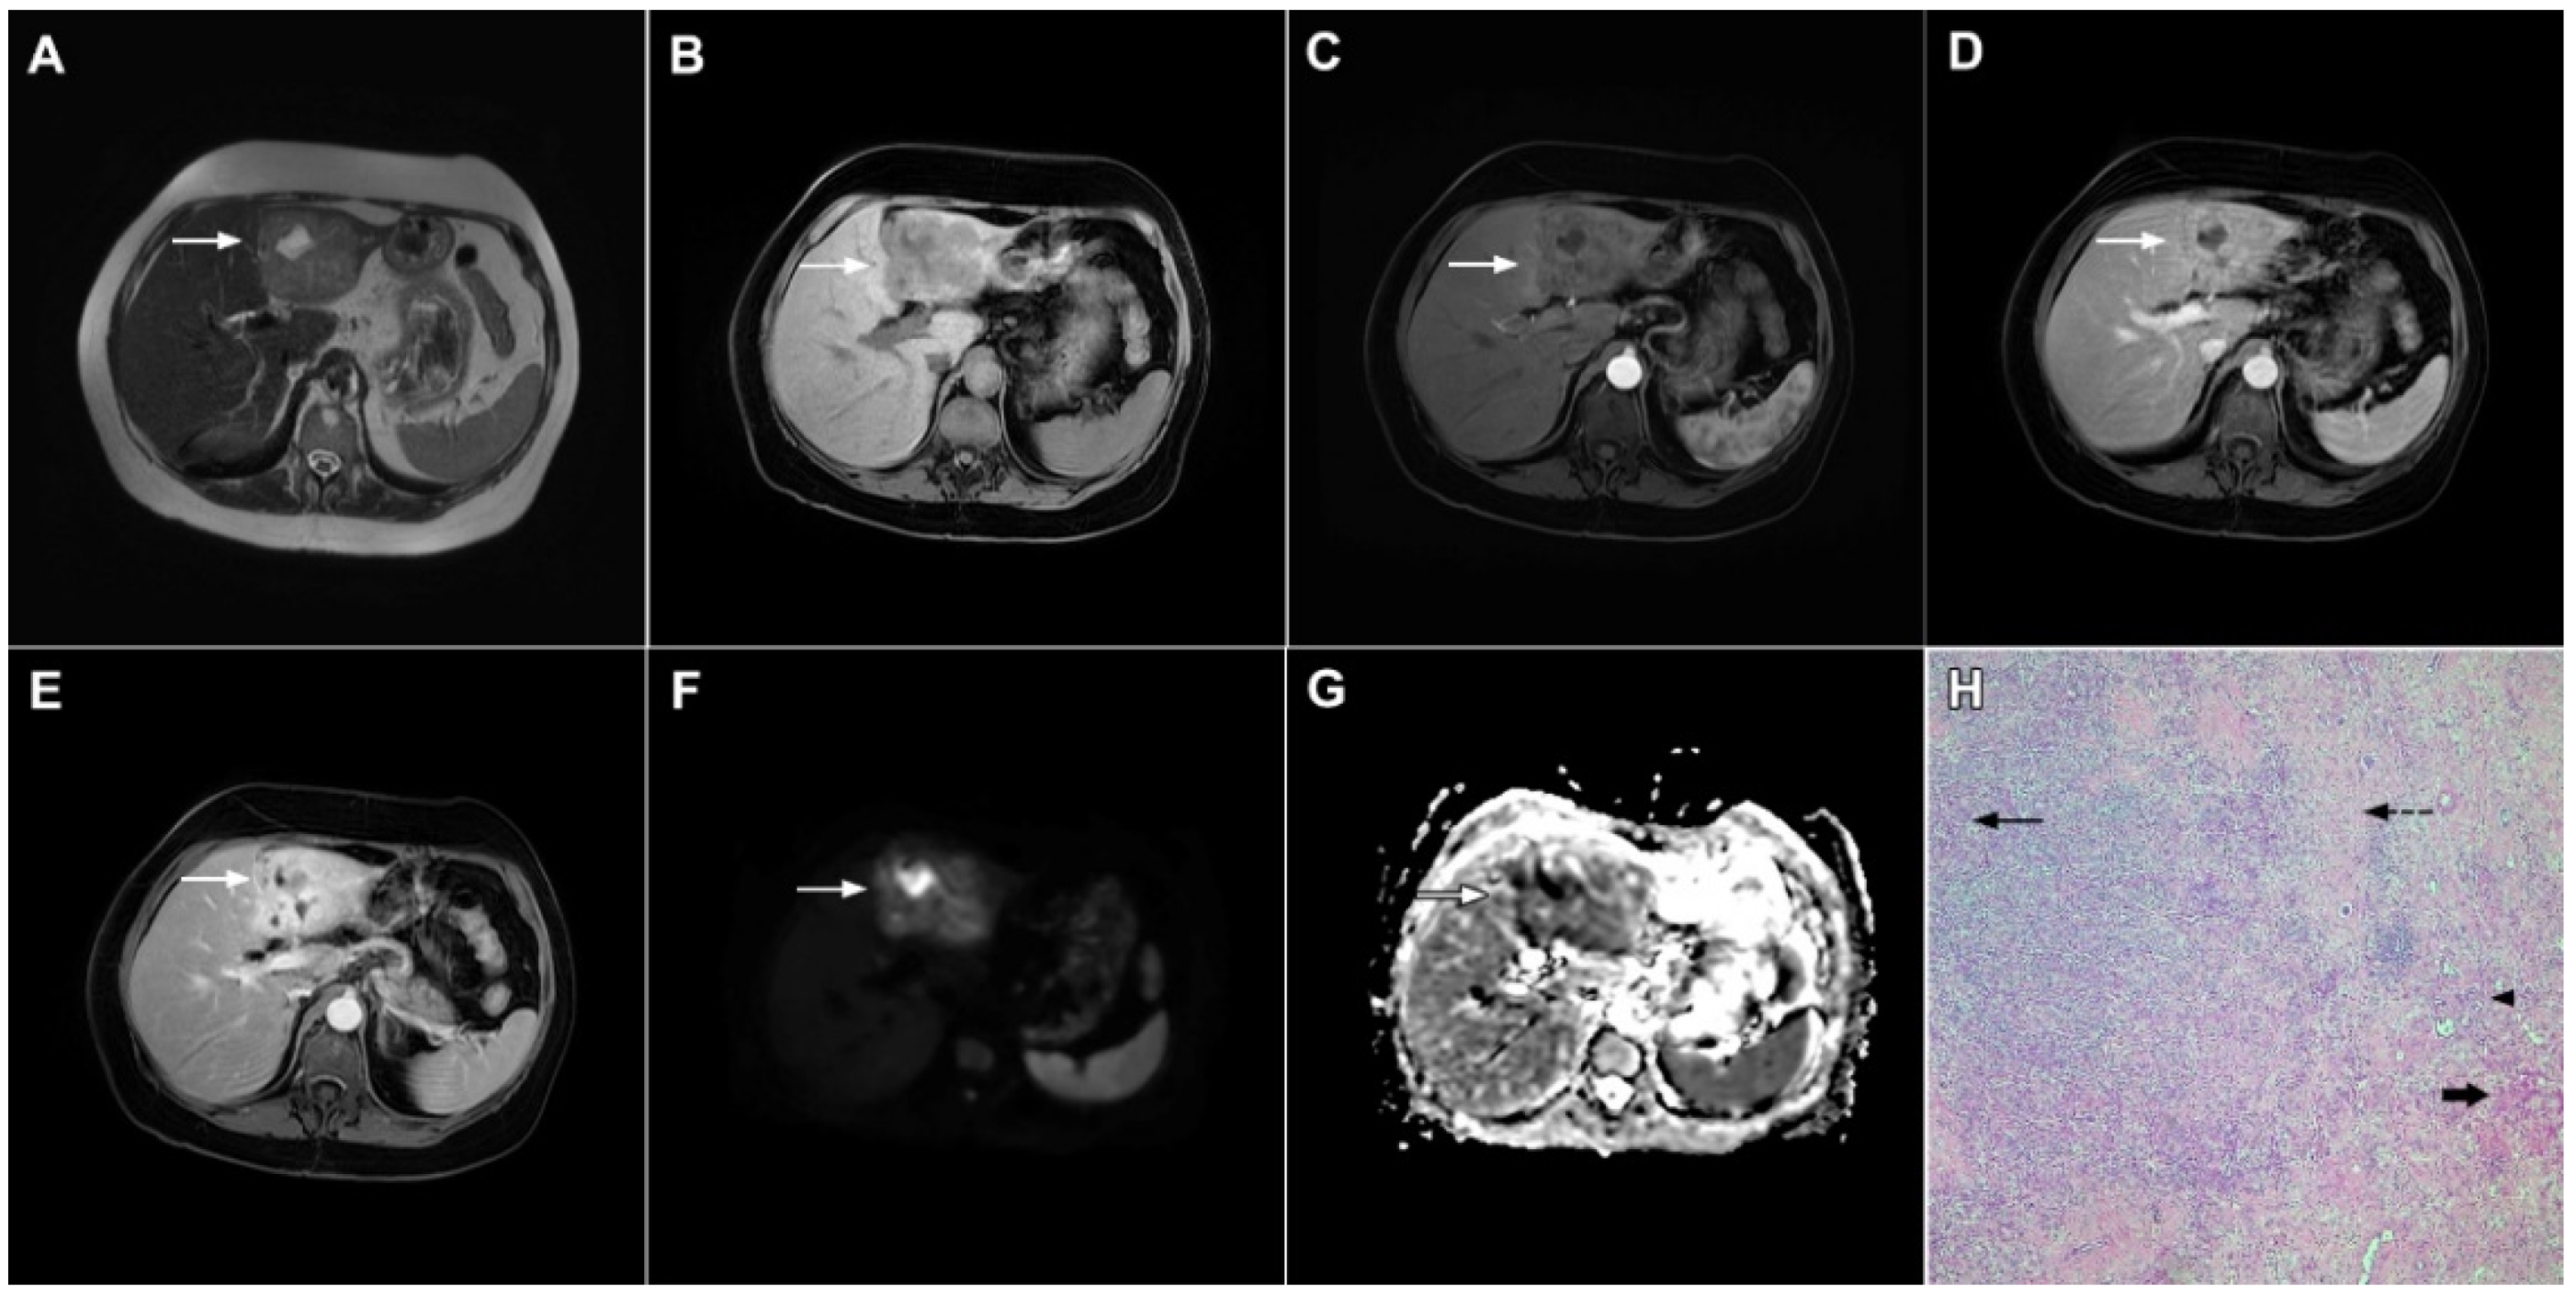

Figure 16.

Solitary hypovascular liver metastasis in a 59-year-old woman. A slightly hyperintense lobulated lesion (arrow) with capsular retraction is seen in liver segments VI and VII in the T2-weighted image (A). The tumor (arrow) is hypointense in the plain T1-weighted image (B) with a slight peripheral enhancement in the arterial phase (C) and a progressive central enhancement in the portal venous (D) and delayed phases (E). In the DWI (F) and corresponding ADC map (G), the tumor (arrow) shows targetoid appearance. Hematoxylin and eosin (H&E) staining showed well-differentiated adenocarcinoma cells of intestinal type (dashed arrow), and normal liver parenchyma adjacent to the metastasis (arrow); original magnification ×40 (H).